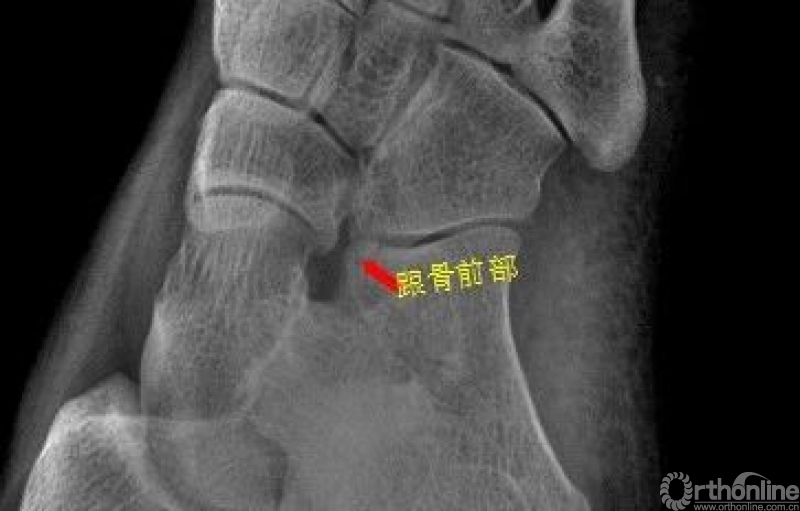

足

右足斜位示 右侧跟骨前部见骨折透亮线。右跟骨前部骨折

Warmreminder: 有一些微小的骨折很容易被忽视。

小妙招1.我会先观察患者精神状态;2.了解受伤部位软组织情况,有时为明确部位,也会亲自触诊。因为有些患者对自己受伤的部位不是很清楚,忘记自己怎么受伤。